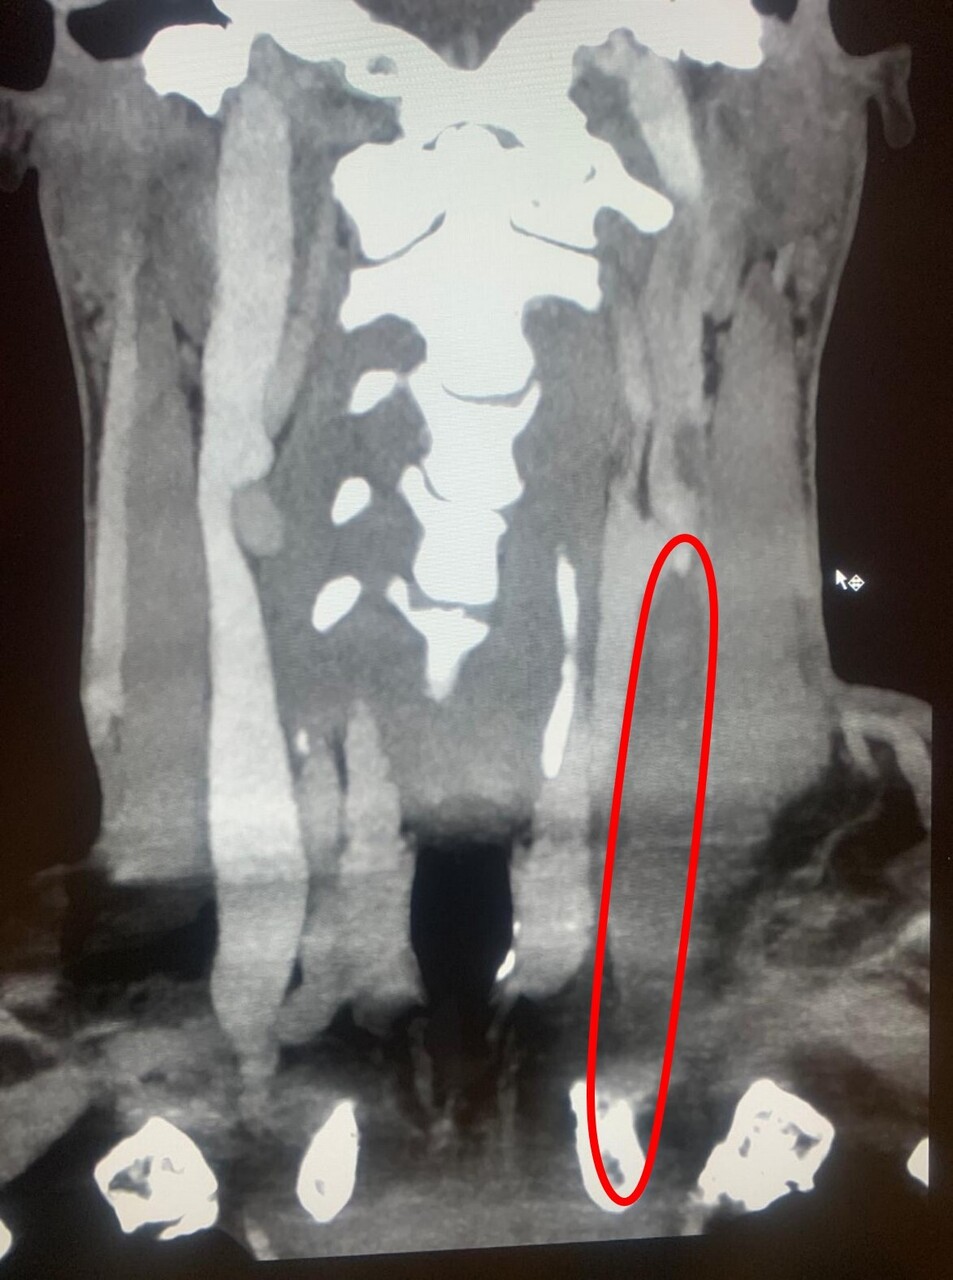

Dans ce contexte anamnestique et clinique, le diagnostic de syndrome cave supérieur avec thrombophlébite profonde est évoqué. Le patient est donc adressé aux urgences de proximité pour bilans diagnostique et thérapeutique. Un angioscanner  thoracique confirme le diagnostic de syndrome cave supérieur (fig. 3) sur masse médiastinale, secondairement étiquetée lymphome B.